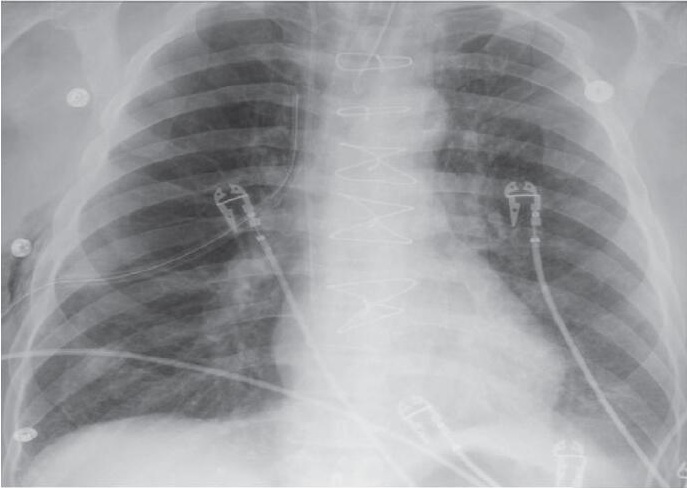

立即行胸腔闭式引流(图3),置入胸引管后,患者胸痛症状很快缓解,肺复张后,再次复查心电图,发现抬高的V1-V4导联已经回落至正常(图4)。再次复查TNI 0.15 ng/ml,较前无明显变化。因而,对于这例胸痛+ST段抬高的患者,诊断不是心肌梗死,不是肺栓塞,竟然是列入其他原因的气胸!

图3 闭式引流后,压缩的肺复张